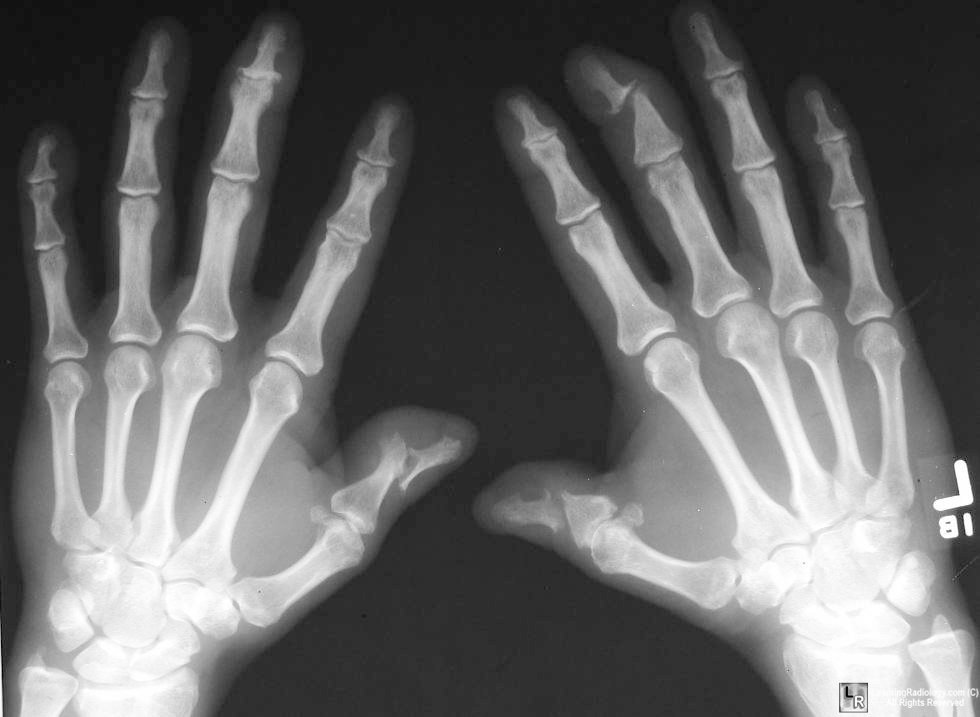

55 Yo M notes pain in his hands and swelling in his fingers, it is hard to flex his fingers now. has a history of long standing low back pain

Q: What is his diagnosis?

Psoriatic Arthritis

Pencil & Cup, dactylitis

joints: wrist, MCP, PIP, DIP